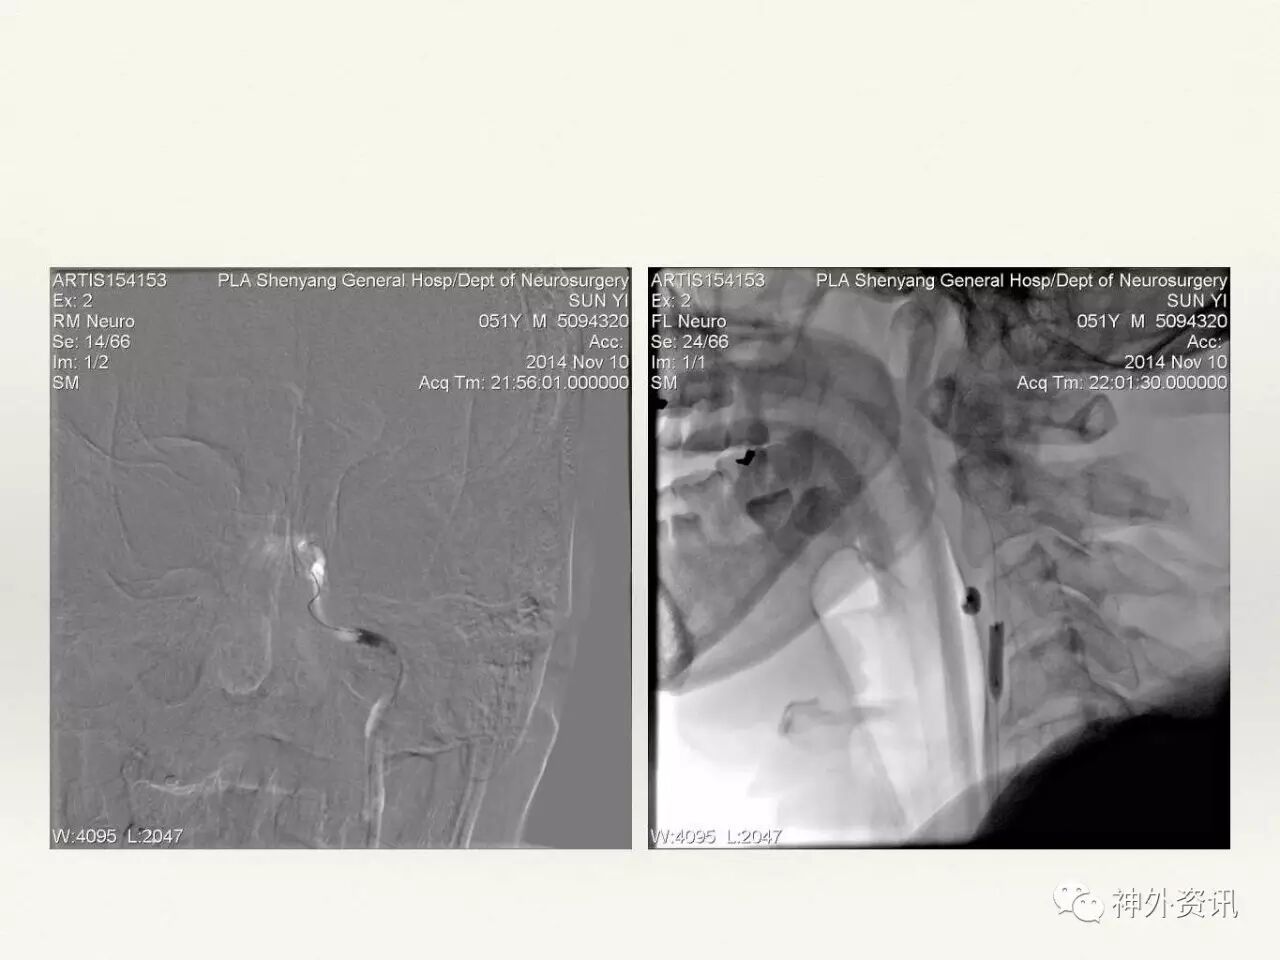

在东北地区率先开展了颈内动脉、大脑中动脉及基底动脉闭塞血管内再通、颅内动脉栓塞急性期取栓、血流导向装置治疗大型宽颈动脉瘤等,对颅内动脉瘤、动静脉畸形、颈动脉及颅内动脉狭窄、颈内动脉海绵窦瘘、硬脑膜动静脉瘘等外科治疗具有较深的造诣。完成脑血管造影8600余例,各类脑血管病介入手术共4500余例,动脉瘤、动静脉畸形、脑肿瘤、脑出血及脑外伤等外科手术1500余例。